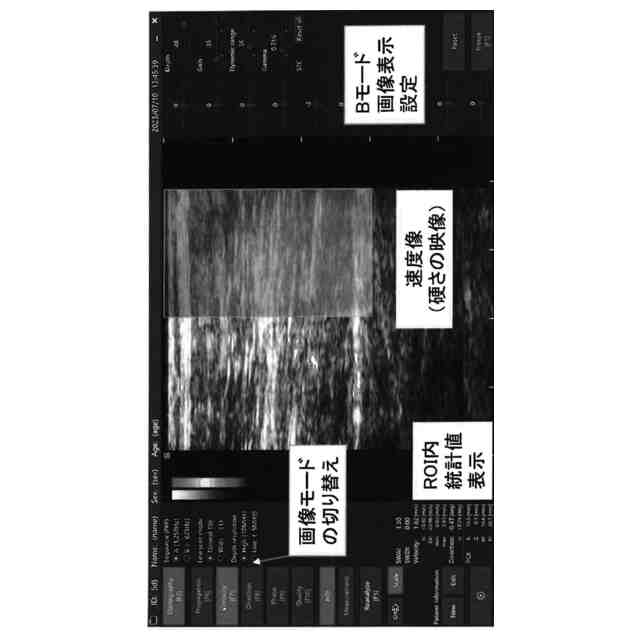

生体物の関節周りの特定の靭帯ないし腱の表面に超音波測定機を押し当て、所定深さにおける靭帯のせん断超音波情報を随時取得し、特定の靭帯のせん断画面をリアルタイム表示するステップと、

その特定の靭帯の伸長先の近傍表面から加振することで、超音波測定機へのせん断波伝播速度とせん断波振幅を特定又は推定するステップと、

特定又は推定したせん断波伝播速度及び振幅を、透過性カラーバーによる二次元マップとして、せん断画面上に重ねあわせ表示するステップと、

連続及び断続時間経過前後における各重ねあわせ表示画像またはその変化を保存するステップと、を具備する方法であって、1次関数モデルを用いた最小二乗誤差法によって推定することを特徴とする、靭帯ないし腱の症状の状態表示方法。